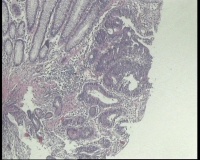

横结肠中部见一增生性肿物大小2.0x1.5厘米,表面糜烂充血,取材2块

2块组织内有1块正常,另一块局灶腺体异型,细胞复层排列,细胞核异型不太大,局灶够高级别吗?